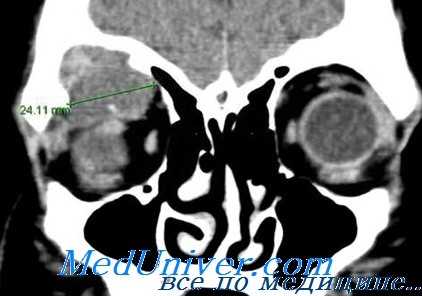

Липома глаза на компьютерной томограмме